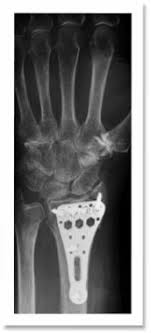

Bei einem instabilen Handgelenksbruch ein Bruch gilt als instabil wenn er mindestens drei der folgenden Kriterien aufweist. Nach 12 Wochen hat sicher aber nichts getan der Knochen ist nicht zusammengewachsen. Wie dem auch sei es wurde konservativ behandelt sprich 12 Wochen Gips.

Radius Fraktur Speichen Bruch Zentrum Fur Handchirurgie Nurnberg